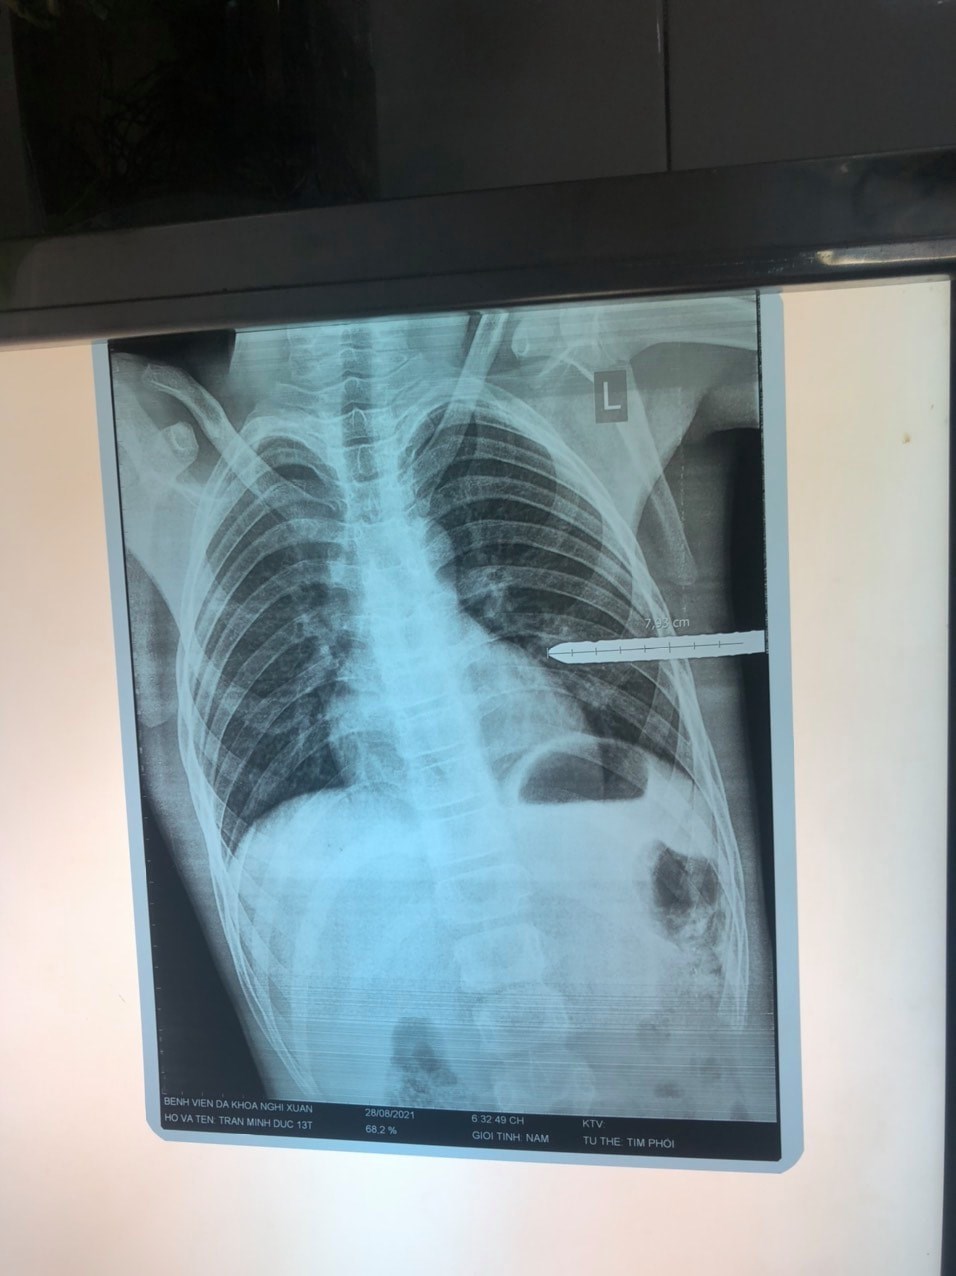

30/08/2021 20:54Nghệ An: Bé trai 13 tuổi bị thanh sắt dài 1 mét đâm xuyên thấu ngực

Ngày 30/8, Bệnh viện Sản Nhi Nghệ An cho biết, đơn vị vừa tiếp nhận và phẫu thuật thành công, kịp thời cứu sống bệnh nhi 13 tuổi bị thanh sắt kích thước lớn đâm xuyên thấu ngực.

Trước đó, vào khoảng 20h20 ngày 28/08, cháu T.M.Đ (13 tuổi, quê huyện Nghi Xuân, Hà Tĩnh) được gia đình đưa tới cấp cứu tại Bệnh viện Sản Nhi Nghệ An trong tình trạng đau đớn, khó thở, da niêm mạc nhợt với một thanh sắt kích thước lớn, dài khoảng 1 mét xuyên vào ngực trái, ở đường nách giữa, khoang sườn 5-6, rỉ máu qua miệng vết thương.

Qua lời kể của gia đình, trước đó, vào lúc 16h cùng ngày, trong lúc chơi đùa, cháu Đ. bị một thanh sắt đâm vào ngực trái. Cháu Đ. sau đó được Bệnh viện huyện Nghi Xuân (Hà Tĩnh) sơ cứu rồi nhanh chóng chuyển ngay đến Bệnh viện Sản Nhi Nghệ An.

Đội ngũ y bác sĩ cấp cứu nhanh chóng tiến hành xét nghiệm, chụp X-quang, siêu âm cho bệnh nhi, chẩn đoán vết thương thấu ngực, tổn thương nhu mô phổi trái. Kíp trực cấp cứu đã tiến hành hội chẩn đa chuyên khoa. Bệnh nhân nhanh chóng được chuyển thẳng từ Phòng Cấp cứu lên Phòng mổ cách ly, cùng phối hợp hồi sức, phẫu thuật xử trí tổn thương ngay lập tức.

Ê kip mổ tiến hành mở ngực, lấy thanh sắt đang cắm vào phổi trái một cách cẩn trọng, tránh gây mất máu ồ ạt và hạn chế tối đa tổn thương. Phổi bệnh nhi bị tràn khí, tràn máu nên ê kip phẫu thuật đã tiến hành bơm rửa sạch màng phổi, kiểm tra, cầm máu kỹ, khâu nhu mô phổi bị tổn thương, đặt một dẫn lưu khoang màng phổi. Sau đó đóng vết thương thành ngực.

Sau 2 ngày theo dõi, hồi sức hậu phẫu, tình trạng cháu Đ. hồi phục tốt, có thể ngồi dậy, vận động nhẹ nhàng.